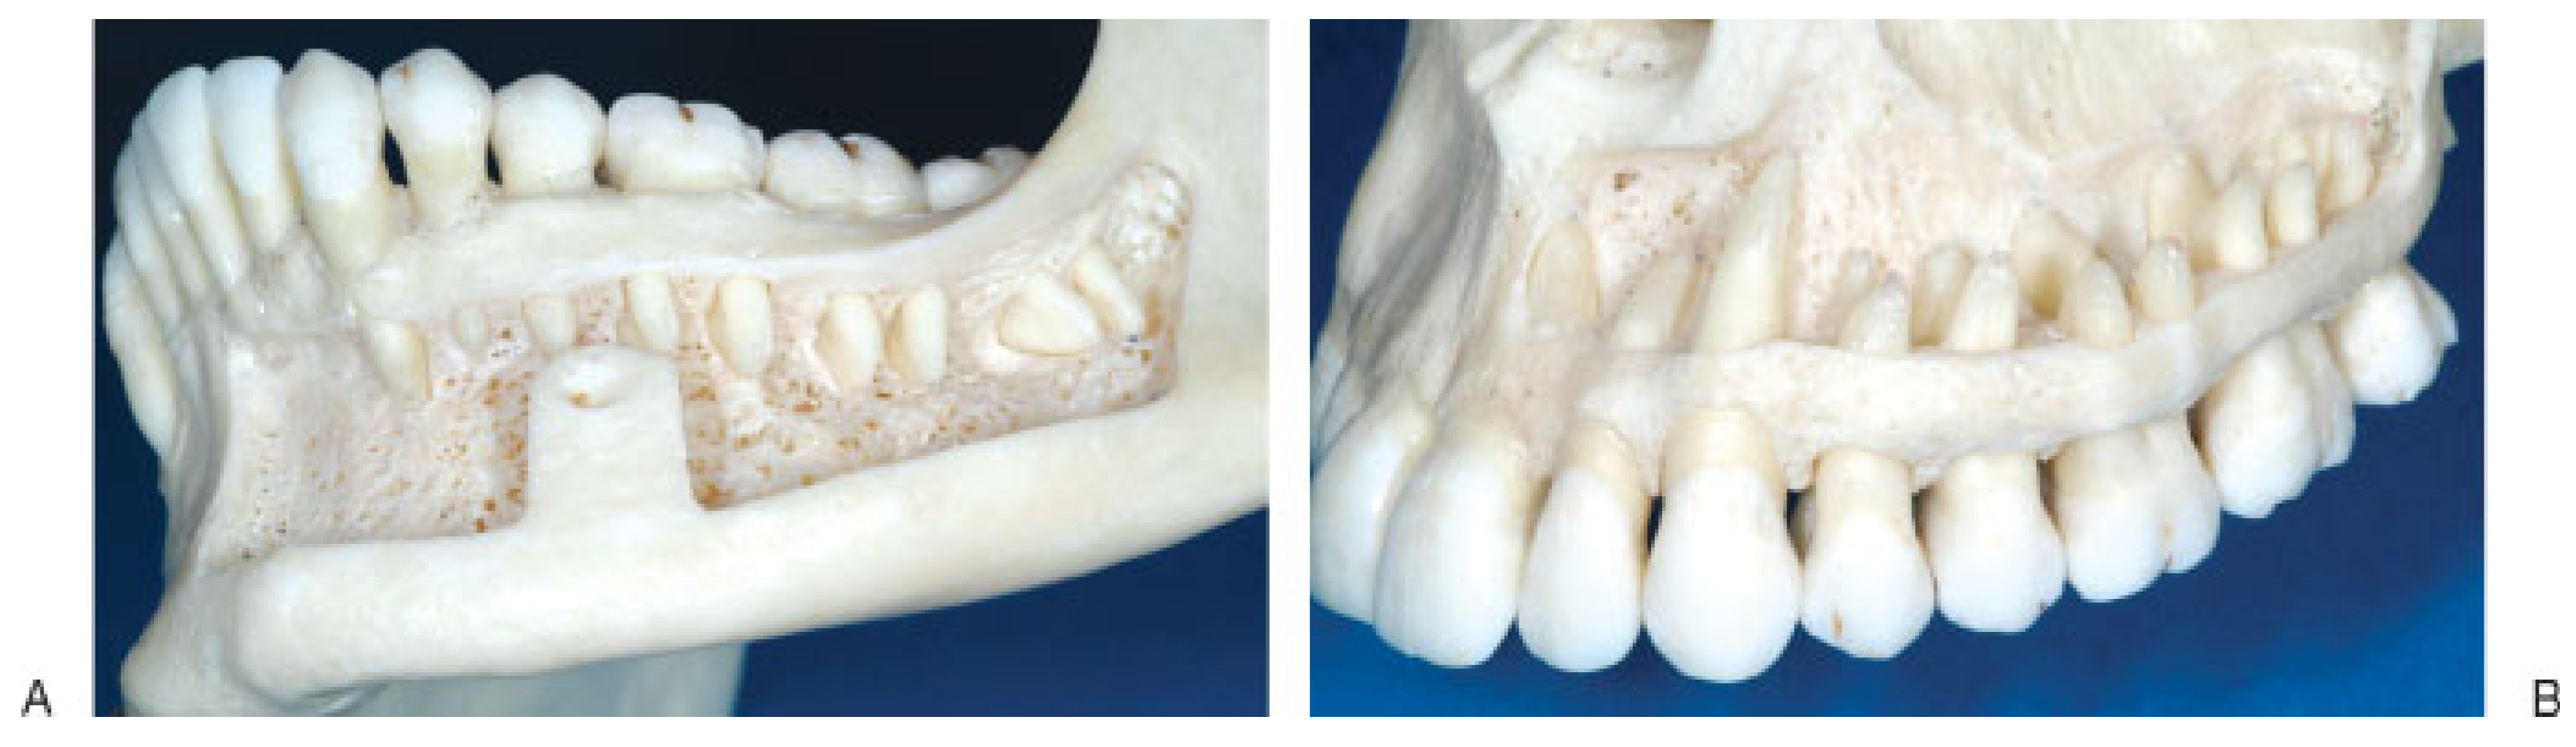

Figure 2. Lower half of the roots of permanent teeth exposed through a bone window in (A) left mandibular quadrant and (B) left maxillary quadrant. Note the width of the interdental bony septae diminishing toward the alveolar limbus and crest.

No attempt should be made to drive MMF screws into the interradicular spaces of the mandibular or maxillary molars due to the minute sagittal and vertical bone dimensions. Moreover the palatine roots of the upper molars would obviate the horizontal insertion depth of the screws (Figure 2B and Figure 3B).